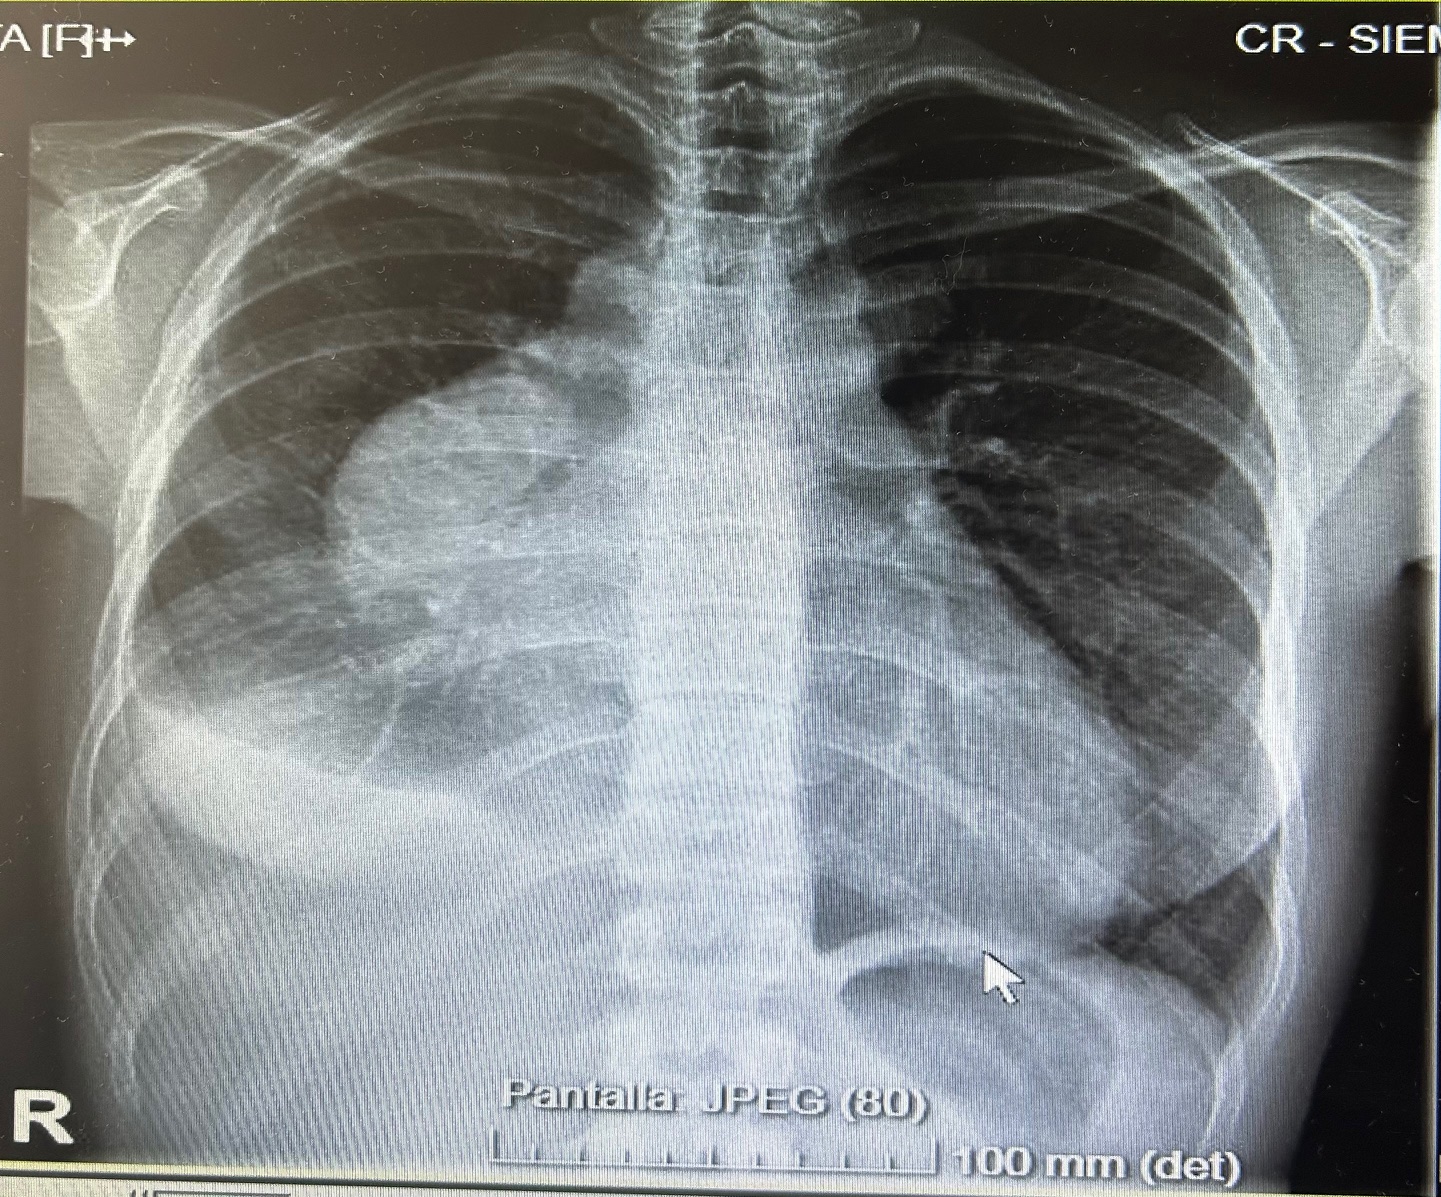

Radiografía de tórax: derrame pleural derecho, ocupación en mediastino anterior. No se observan infiltrados claros.

La ecografía clínica desempeñó un papel fundamental en la evaluación inicial del paciente, permitiendo una detección rápida y precisa de hallazgos que guiaron la toma de decisiones clínicas. La ecocardioscopia realizada reveló un derrame pericárdico moderado, sin signos de taponamiento cardíaco y un derrame pleural derecho significativo. Estos hallazgos fueron esenciales para descartar la presencia de un cuadro obstructivo que pudiera haber requerido una intervención inmediata. Además, la ecografía permitió valorar el estado hemodinámico de la paciente de forma no invasiva, asegurando que el derrame pericárdico no comprometiera la función cardíaca. En la radiografía de tórax se objetiva una masa mediastínica. La capacidad de detectar y cuantificar de forma precisa tanto el derrame pleural como el pericárdico sin necesidad de esperar a pruebas más complejas, permitió que la paciente fuera ingresada de manera adecuada para un estudio exhaustivo y sin demoras innecesarias.